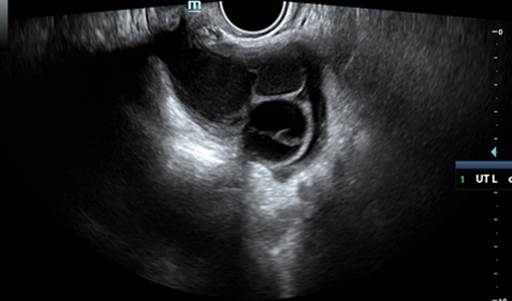

La evaluación ecográfica reportó el útero sin patología. En ovario derecho: se evidenció imagen ecomixta, predominantemente sólida, redondeada, de bordes regulares de 67 x 64 mm, con áreas hiperecogénicas centrales (Figura 1), score doppler 2, sugestiva de teratoma. En ovario izquierdo: se evidenció imagen multilocular ovalada, anecoica (vidrio esmerilado), con tabique completo de 2 mm, paredes internas lisas, bordes regulares, de 67 x 42 mm (Figura 2), score doppler 1.

Figura 2 Ovario izquierdo con imagen multilocular ovalada, anecoico (vidrio esmerilado), tabique completo de 2mm, de dimensiones 50 x 42mm.